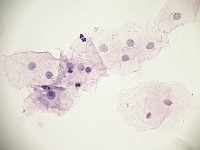

Cervical Cancer Screenings: The "PapDetector" can be used for the initial screening in detecting cervical cancer. Its ability to classify different cellular structures could provide invaluable assistance in large-scale cervical cancer screening tests, making the entire process more efficient.

Medical Research: Scientists and researchers can use this model to identify and further study these cellular structures. This could improve the understanding of various conditions related to cell abnormalities, thus leading to new treatments or diagnostic methods.

Training Medical Students: The "PapDetector" can also serve as a learning tool for medical students, enabling them to visually learn and identify cell structures that denote normal and abnormal cases.

Pharmaceutical Development: The computer vision model could be utilized in the pharmaceutical industry to screen the effects of drug treatments on cell morphology – highlighting normal, HSIL, LSIL, ANORMAL, Koilocytes changes in response to pharmaceutical compounds. This information would be useful in drug development and efficacy trials.